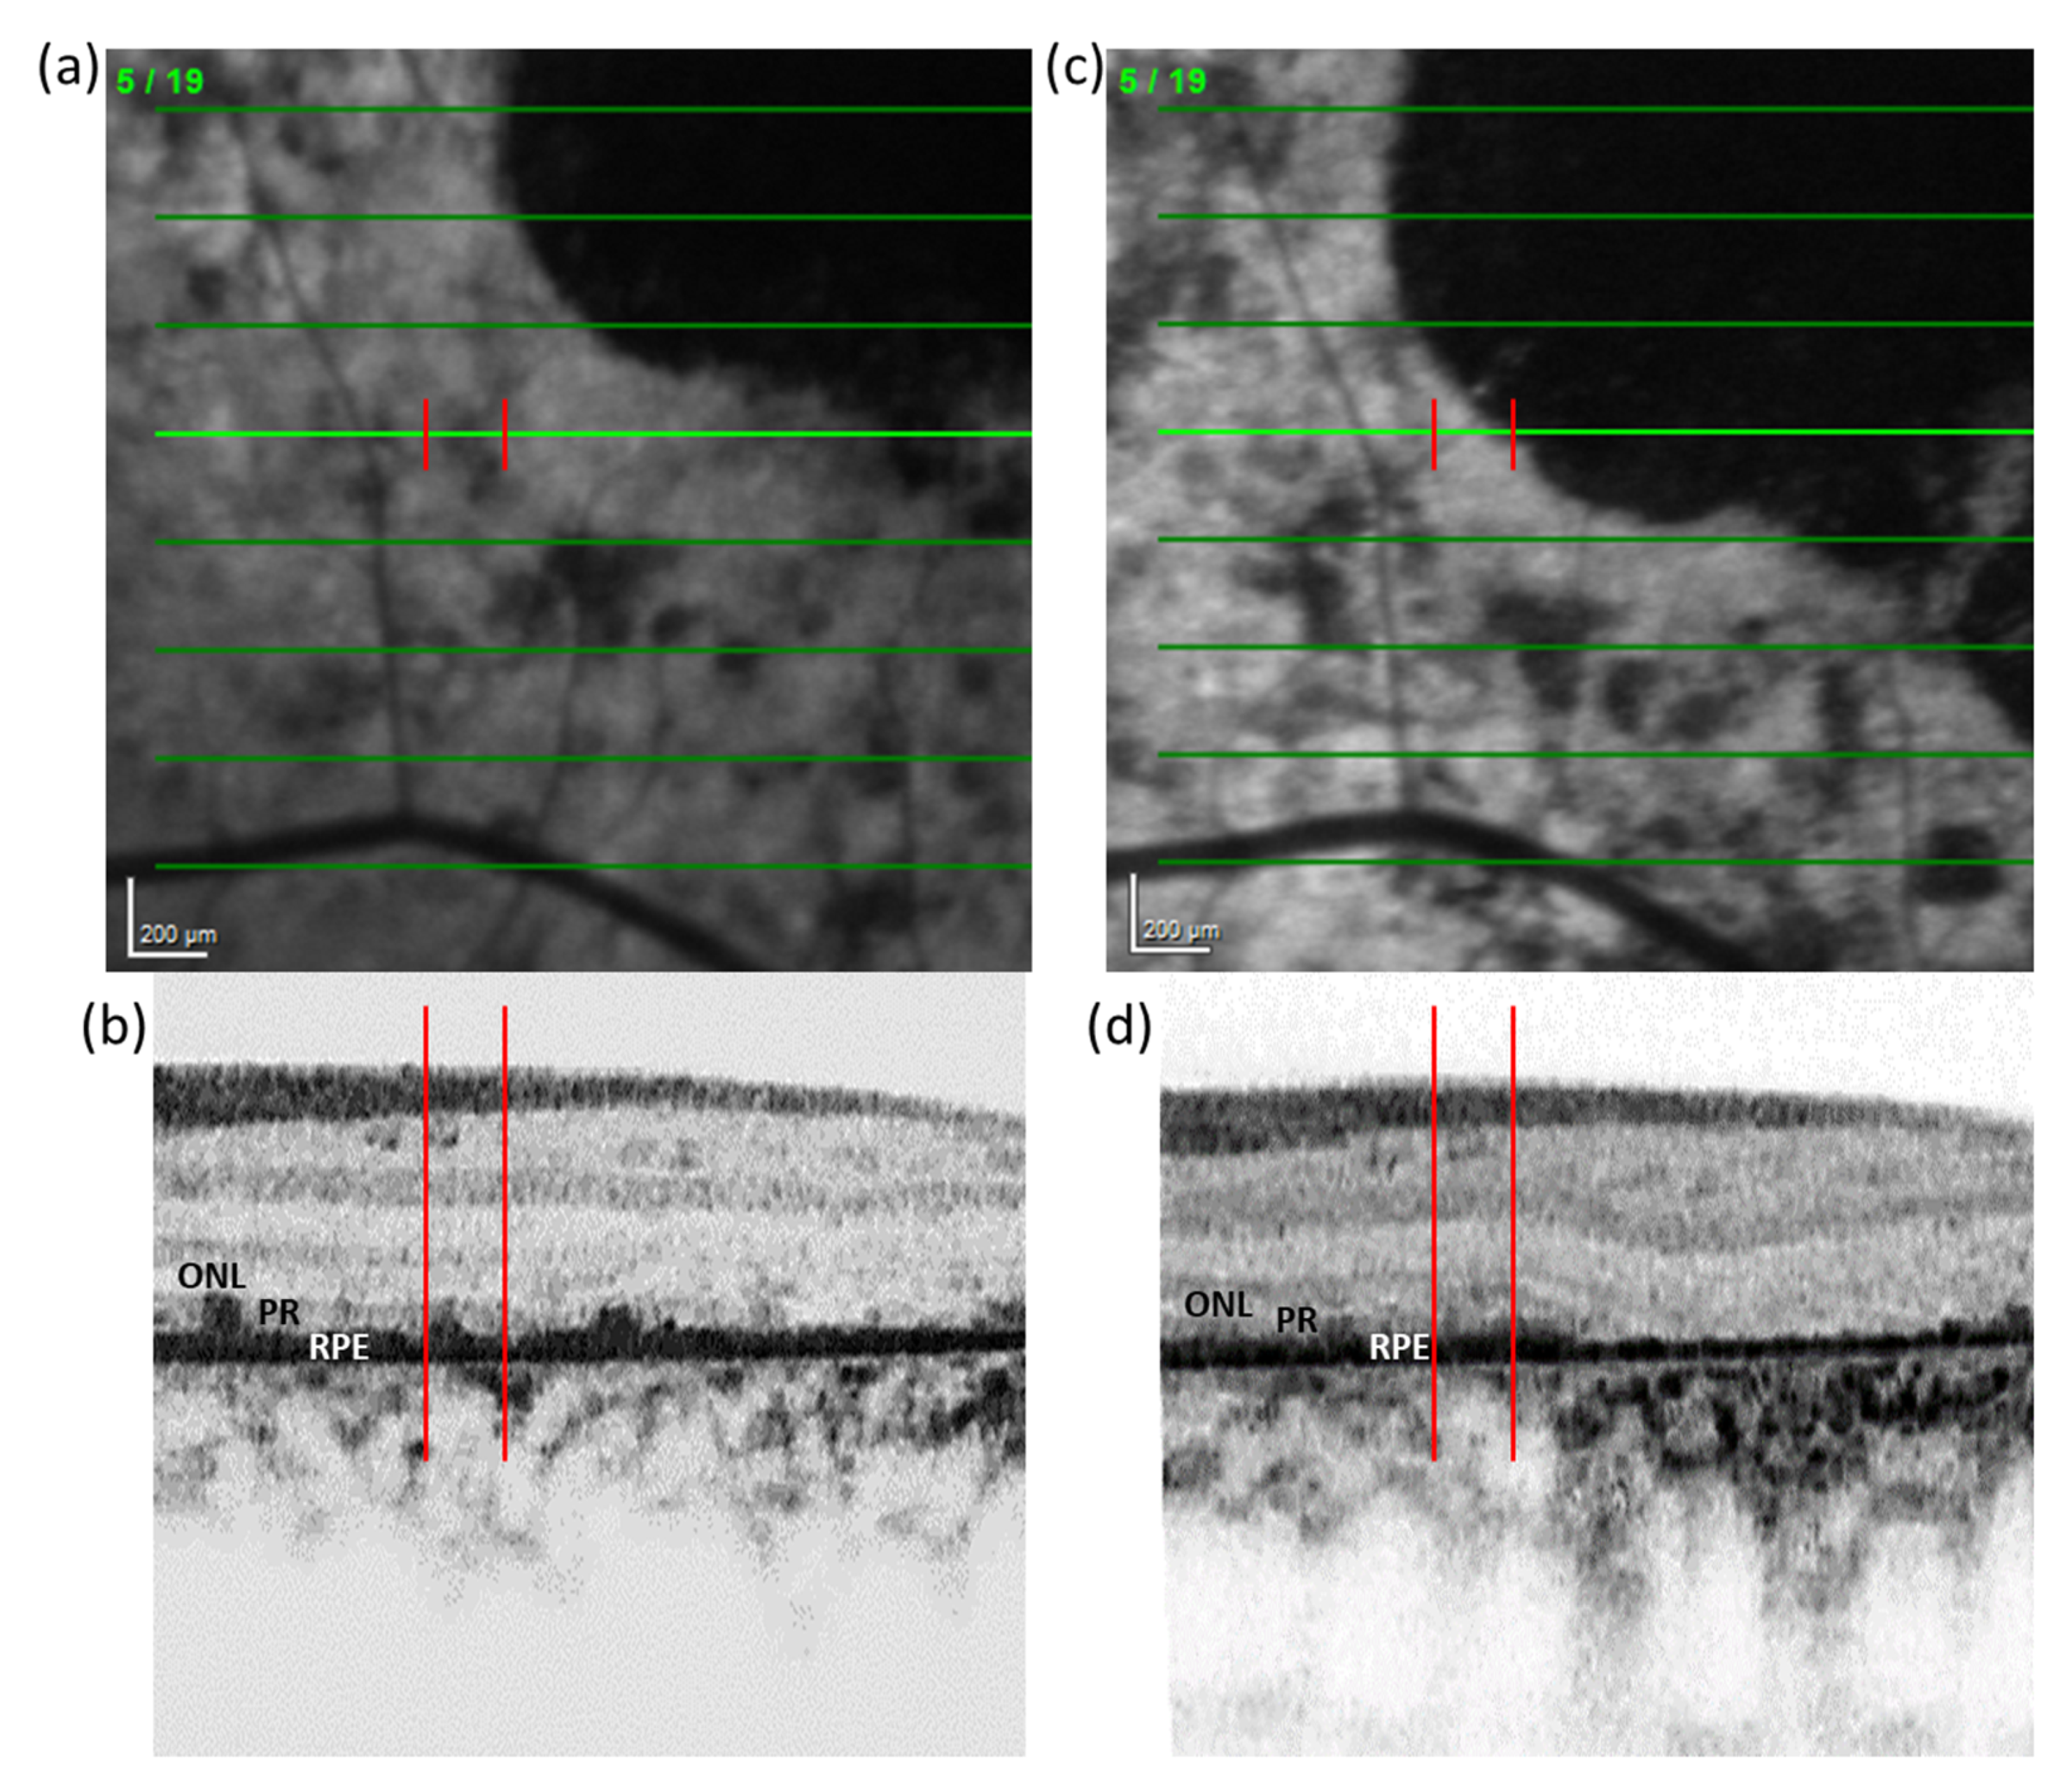

3.5. Qualitative Analysis of SD-OCT Data at FRA